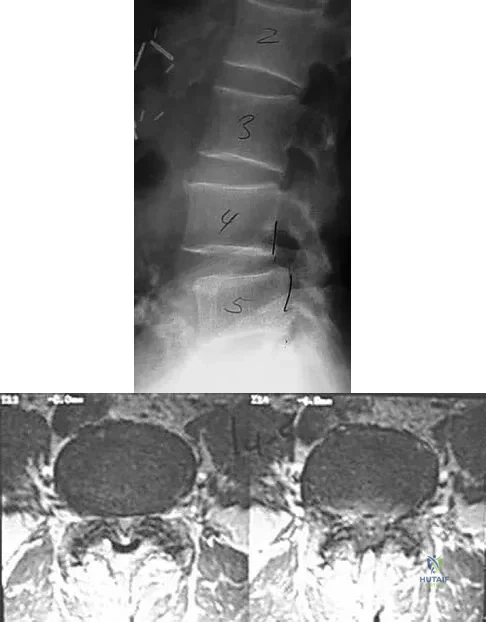

An otherwise healthy 70-year-old man has back and bilateral leg pain in an L5 distribution that is aggravated by standing more than 10 minutes or walking more than 100 feet. He has to sit to get relief. Neurologic and pulse examinations are normal. A radiograph and MRI scan are shown in Figures 4a and 4b. Treatment should consist of

Explanation